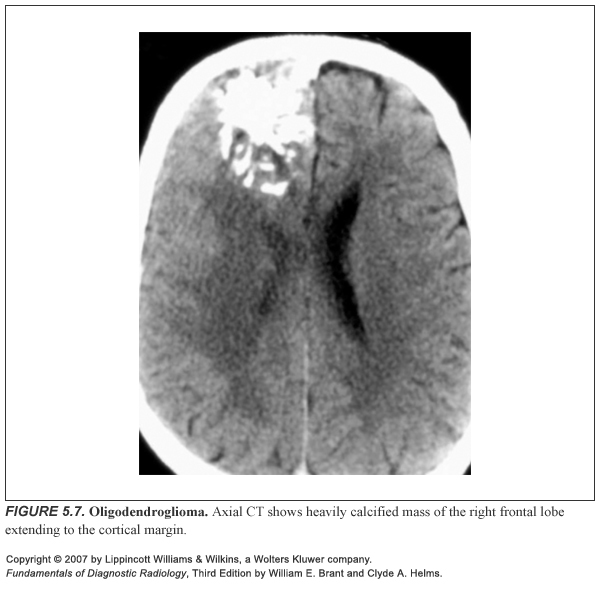

DDx for a calcified glial tumour?

Oligodendroglioma: 75% are Ca++ Ependymoma Astrocytoma (commonest cause, but purely because it is the commonest glial tumour) Glioblastoma multiforme